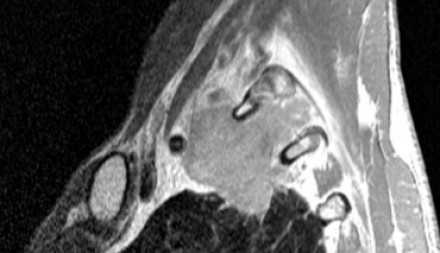

Рак Панкоста

Типичные проявления рака Панкоста следующие:

- боли, обусловленные инвазией в плечеголовное сплетение.

- синдром Горнера

- деструкция костных структур

Выполнение МРТ приоритетнее в связи с лучшим мягкотканным контрастом в сравнении с КТ.

На Т1-изображениях представлен пациент с раком Панкоста Т3-стадии в связи с тем, что поражены корешки только Th1, Th2

- ПкА = подключичная артерия,

- ПЛМ = передняя лестничная мышца.

(Courtesy of Wouter van Es, MD. St. Antonius Hospital Nieuwegein, The Netherlands)